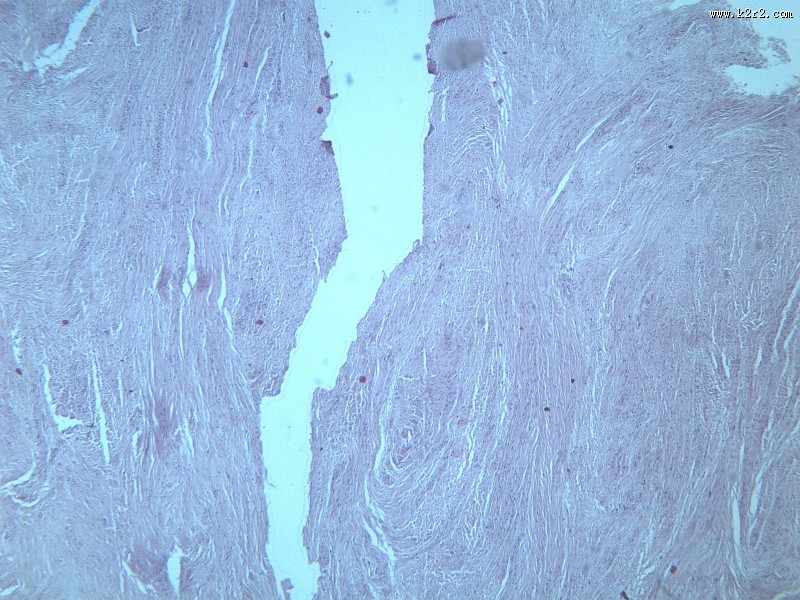

纤维瘤大全 - 第4张

纤维瘤大全

乳腺纤维腺瘤

纤维肉瘤大全

医学

显微切片

肿瘤

fibroma

纤维瘤